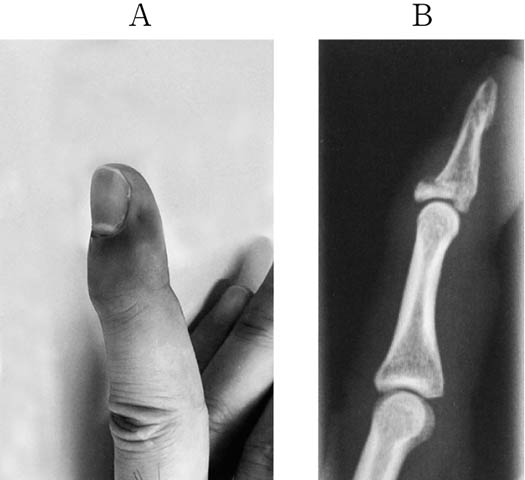

36歳の男性.手にバスケットボールが当たって受傷した.来院時の手指の写真とエックス線単純写真とを下に示す.この病態として

- 1.槌 指

- 2.ばね指

- 3.ボクサー骨折

- 4.ムチランス変形

- 5.Bennett骨折

解答: 1